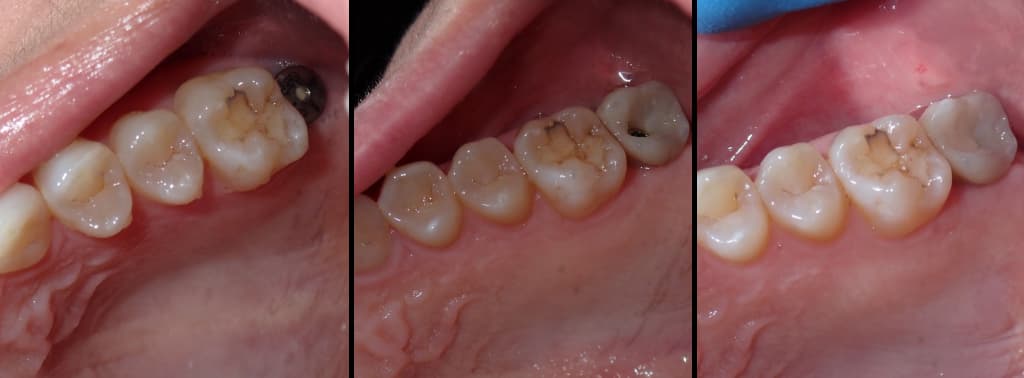

Implant Image Process

implants-before-after